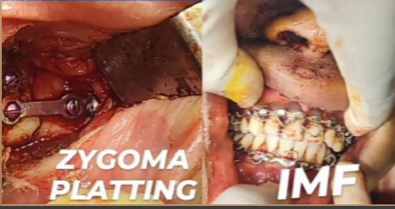

Submental Intubation

IMF

Platting